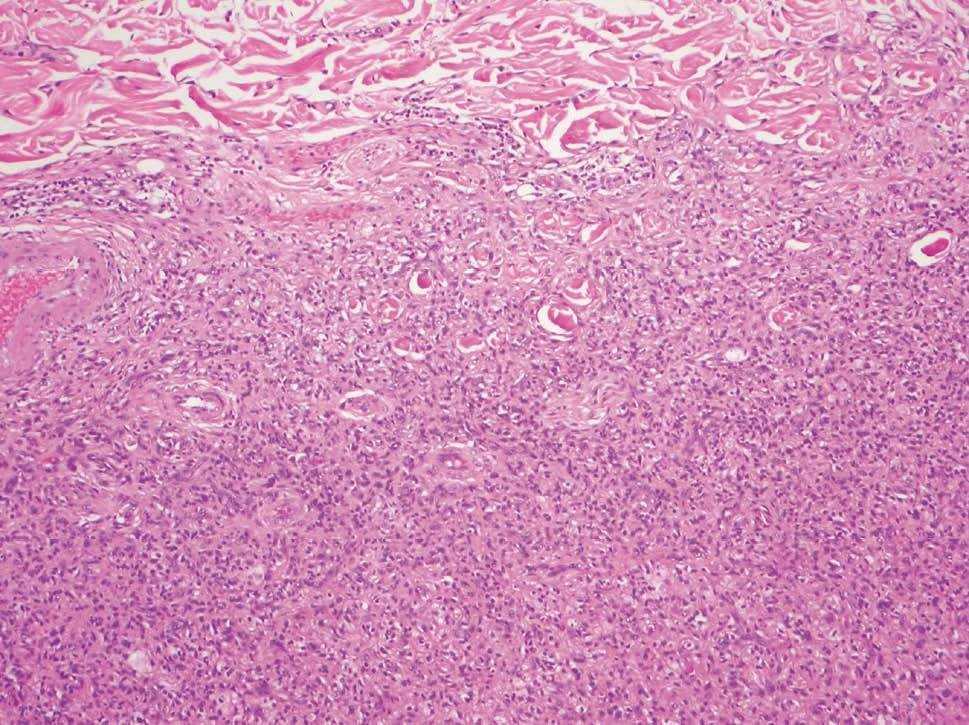

El estudio histológico mostró una tumoración bien delimitada, no encapsulada, localizada en dermis reticular y tejido celular subcutáneo (fig. 2). La lesión estaba compuesta por células de hábito fibrohistiocitario constituyendo áreas de densidad celular heterogénea. En la periferia de la lesión, las células fusiformes y ovoideas se entremezclaban con haces engrosados y bolas de colágeno eosinófilas (fig. 3). La zona central de la lesión estaba constituida por células poligonales xantomatizadas de mayor tamaño, de núcleo excéntrico y citoplasma repleto de grasa, rodeadas de un colágeno hialinizado que las individualizaba de otras células (fig. 4). La inmunohistoquímica resultó positiva para el antígeno fibrohistiocitario común (cd68) y al factor XIIIa, siendo negativo para el cd34.

Figura 2. Panorámica de la lesión. (Hematoxilina-eosina.)

Figura 3. Periferia de la lesión con células fusocelulares entremezcladas con haces de colágeno engrosados (Hematoxilina-eosina, x100).